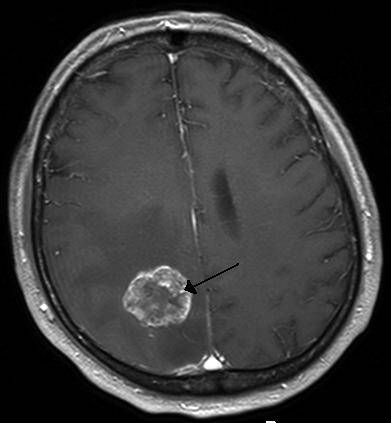

Beyin tümörü uyku hali. Yetişkinlerde ikincil beyin tümörleri birincil beyin tümörlerinden çok daha yaygındır. Ancak şikayetler çok daha çeşitlilik gösterebilir. 1925 yılından beri bilinen bu beyincik tümörü çok ayrı hücresel ve klinik özellikeri olan ve oldukça habis karekterli bir beyincik tümör tipidir beyinciğin çocuklarda en sık tümörü olup tüm primer beyin tümörlerininin 4 10 teşkil ederler. Patoloji alındı ondada tam teşhis konulmadı.

Sürekli uyku hali i̇çin hangi doktora gidilmeli. Eşim iki ay önce beyin tümörü teşhisi kondu. çekilen emar ve tomografi sonucuna göre tümör dendi. Bu şikayetler beyin tümörü belirtisi olabilir.

Gün içinde halsizlik ve sürekli uyku hali sabahları ise baş ağrısı ve ağız kuruluğu ile uyanmalar tipiktir. Uyku tüm tümörlerin ortak belirtisi değildir fakat bazılarında görülür. Beyin tümörü hastalarının son günleri nasıl anlaşılır. şimdi radyoterapi ve kemoterapi alıyor.

Uykuyu kontrol eden sinirler beyin sisteminde yer aldığı için sürekli uyku problemini çözmek için nöroloji bölümüne gitmeniz gereklidir. İkincil beyin tümörleri en sık kanser öyküsü olan kişilerde görülür. Denge kaybı uyku hali gözde görme sorunları duyma sorunları el ya da ayaklarda his sorunları ruhsal değişiklikler halüsinasyonlar görebilir yemek yeme sorunları yutkunma sorunları yemek yeme sorunları halsizlik trombosit düşüklüğü lökosit. Sadece uyku hali be yorgunluğu vardı.

Sonrasında bulantı kusma şuur dalgalanmaları uyku hali baş dönmesi ve nöbet geçirme vücudun farklı bölgelerinde kuvvetsizlikler iştahsızlık unutkanlık gelmektedir. Bunların en başında yeterince uyumamaktır. Ancak çocukluk yaşı tümörlerin 15 20 sini teşkil etmektedir. Beyin tümörü uyku yapar mı.